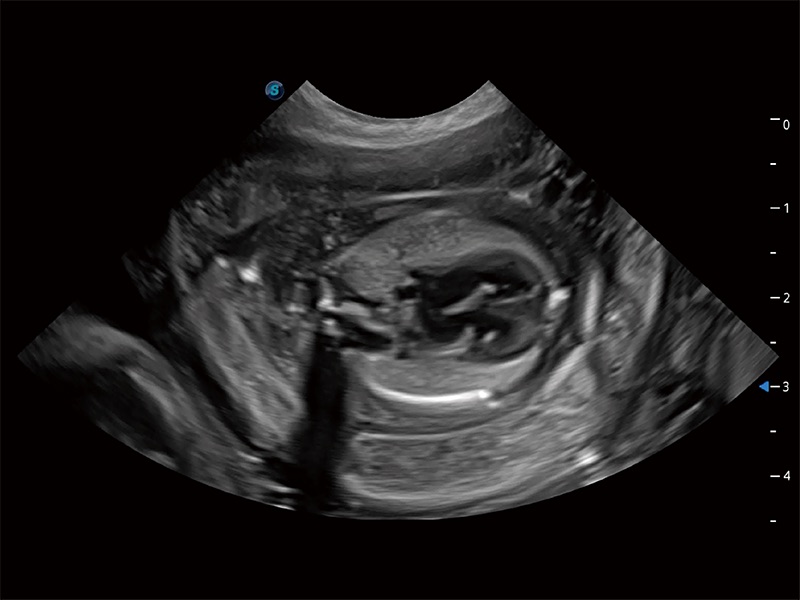

动物是人类最亲密的朋友和最值得信赖的伙伴。DB中国旗舰官方网站也一直致力于探索动物专用的超声影像解决方案。全新推出的ProPet系列,是DB中国旗舰官方网站在动物超声影像智能化、专业化、精准化的一次跨越式革新。动物不能用言语来表述自己的不适,通过超声影像,ProPet系列搭建了动物医生与不同物种沟通的“桥梁”,为动物医生注入了“治愈之力”。 ProPet 80 是DB中国旗舰官方网站匠心打造的一款高端动物专用彩超,采用性能卓越的全新硬件架构,极大提升超声系统的运行效率和数据处理能力,帮助动物医生从容应对日益增多的挑战性病例和日益多样化的临床需求。

高性能和先进的临床应用工具可以为动物医生提供临床信心。ProPet 80 搭载了先进的腹部和浅表应用工具,帮助医生在日常临床实践中发挥前所未有的作用。

ProPet 80 配备了丰富的心脏探头群、先进的成像技术和专业的心脏测量工具,可帮助动物医生为不同体型和生理结构的动物提供心脏和心肌功能的全面评估。

ProPet 80 专为动物医生设计,对不同的动物体型和生理结构作出了针对性的优化。通过动物影像专用软件,可满足个性化的应用需求,帮助动物医生获得更精确的诊断数据。

ProPet 80 全新的动物超声智能软件和丰富的探头群,为动物医生提供了高清晰度和精细分辨率的图像,无论在宠物、马科、畜牧还是实验室动物等应用中都可以轻松应对,为您的日常工作带来满意的体验。